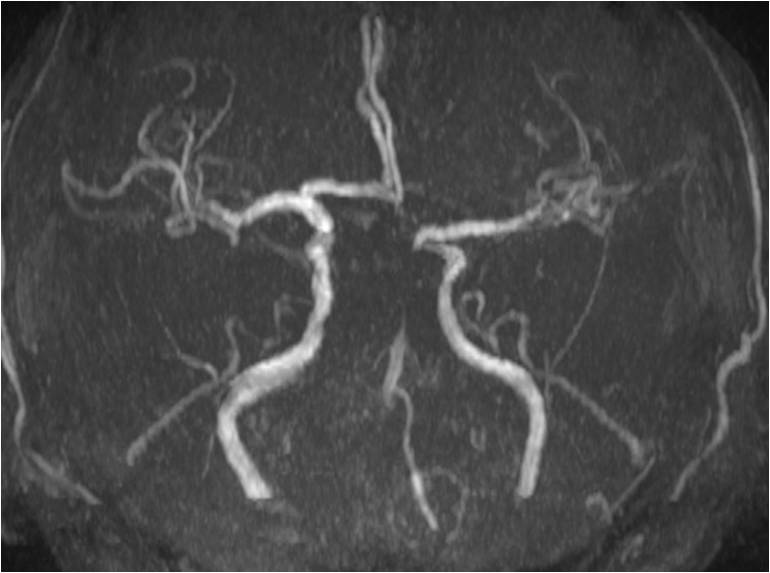

》昏迷后行头MRA检查。

▼8:36头MRA

》11:56头MRA。

▼11:56头MRA

▼术前头MRA

▼术后24小时头MRA